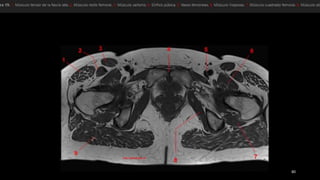

• músculo glúteo mayor (GMa)

• músculo tensor de la fascia lata (Tfl anterior y la

fascia lata (FL) situada entre ambos músculos

• «bandeleta de Massiat» (BM)

• glúteo medio (GMe) y glúteo menor (GMI)

• trocánter mayor (TM)

• El músculo glúteo mayor (GMa).

• músculos semimembranoso (sm), semitendinoso (st)

y la cabeza larga del bíceps femoral (elb).

• músculo semimembranoso tiene su propio tendón

(1).

• semitendinoso y la cabeza larga del bíceps se originan

en la cara lateral de la tuberosidad isquiática -en un

tendón común (2).

• nervio ciático (NC). TM, trocánter mayor.

• músculo glúteomayor (GMa) • músculo tensor de la fascia lata (Tfl anterior y la fascia lata (FL) situada entre ambos músculos • «bandeleta de Massiat» (BM) • glúteo medio (GMe) y glúteo menor (GMI) • trocánter mayor (TM)

• El músculoglúteo mayor (GMa). • músculos semimembranoso (sm), semitendinoso (st) y la cabeza larga del bíceps femoral (elb). • músculo semimembranoso tiene su propio tendón (1). • semitendinoso y la cabeza larga del bíceps se originan en la cara lateral de la tuberosidad isquiática -en un tendón común (2). • nervio ciático (NC). TM, trocánter mayor.